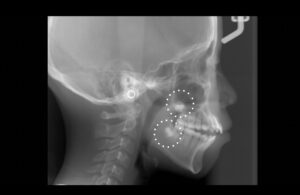

セファロレントゲンで親知らずが存在することが確認できる。親知らずを抜歯したスペースを利用して矯正治療を行いたいが、

初診時は13歳でありすぐに抜歯することができないと判断。